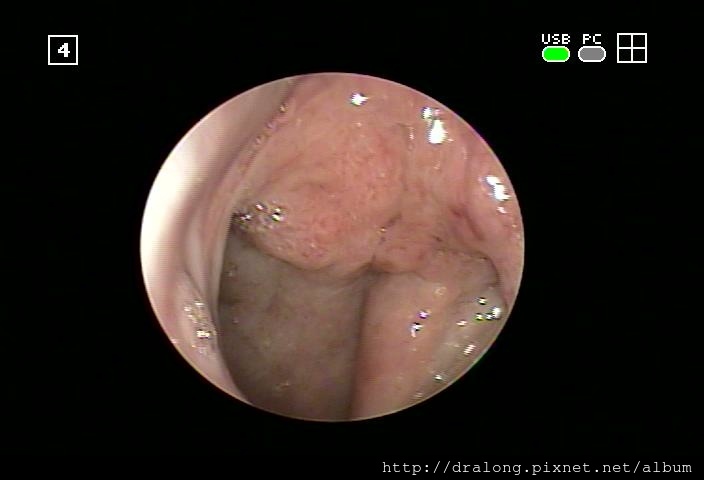

急性鼻咽發炎